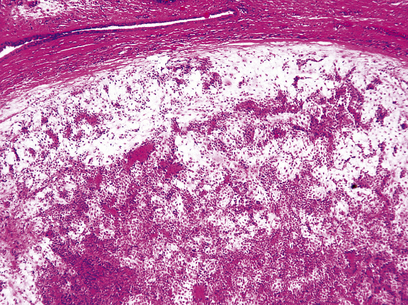

Pleomorphic adenoma

At least two-thirds of all salivary tumours are accounted for by the pleomorphic adenoma or ‘mixed tumour’, and over 80% occur in the parotid gland. As the name implies, this has a varied histological appearance and is composed of a mixture of stromal and epithelial elements (Fig. 15.3). The myxoid stroma, which is rich in proteoglycans, is thought to be produced by myoepithelial cells; thus, despite its biphasic appearance, it is a purely epithelial neoplasm. Occasionally the stroma has a cartilaginous appearance. Pleomorphic adenomas are essentially benign tumours but are prone to local recurrence if surgical removal is incomplete. The facial nerve is vulnerable during attempts at surgical removal. A very small proportion undergo malignant change and are capable of metastasising; these are termed malignant mixed tumours.

image

Fig. 15.3 Pleomorphic salivary adenoma. These benign neoplasms consist of a mixture of proliferating epithelium and mucinous connective tissue resembling cartilage surrounded by a capsule of fibrous and compressed salivary tissue.